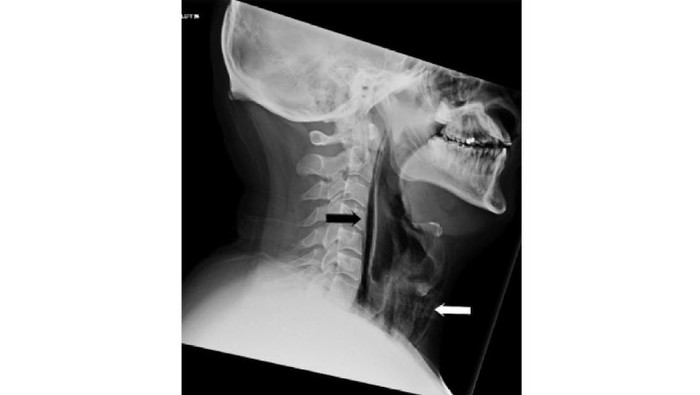

Dikutip dari NDTV, para dokter mengatakan bahwa ada aliran udara yang terperangkap di beberapa jaringan tenggorokan dan merusaknya. Kasus pecahnya faring secara spontan seperti ini sangat jarang terjadi. Biasanya disebabkan oleh muntah, retching atau kontraksi otot respirasi, batuk berat, hingga trauma.

Pria itu langsung mendapat perawatan untuk menghindari risiko atau perkembangan infeksi leher dalam. Dia dipasangkan selang makanan dan antibiotik.